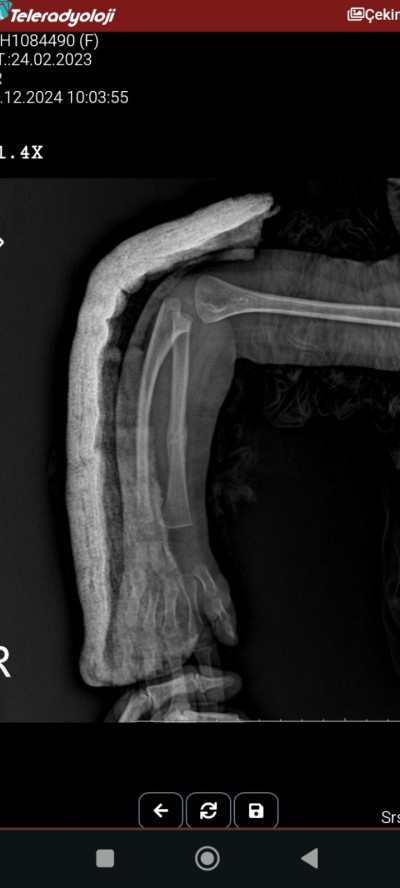

3 hafta önce kızım duştu kolu kırıldı alçıdaydı bugün doktor açtı baktık kolu hafif yamukluk var gibi geldi doktora sorduk yılar sonra düzelir dedi sizcede bu durum normal mi bakarmısınız

Röntgen de düz duruyor ama kolu yomuk gibi anlamadım

Aşağıdaki fotoda yamukluk görünüyor cnm Dr ztn daha çocuk bence de ilerledikçe düzelecektir inşallah